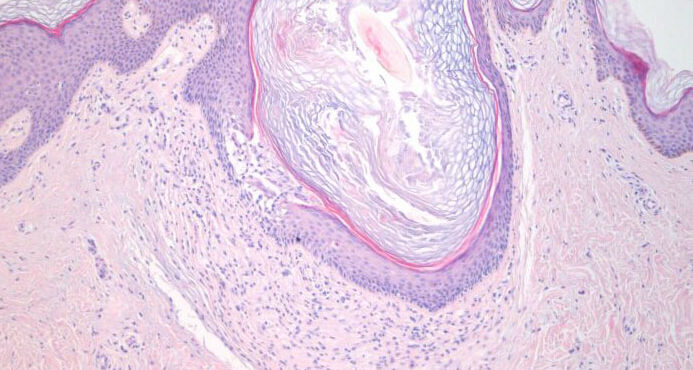

Read MoreForeign body reaction = ارتكاس للجسم الاجنبي Foreign Body Reactions Foreign substances, when injected or implanted accidentally into the skin, can produce a nonallergic foreign-body reaction or, in persons specifically sensitized to them, an allergic response (. In addition, certain substances formed within the body may produce a nonallergic foreign-body reaction when deposited in the […]